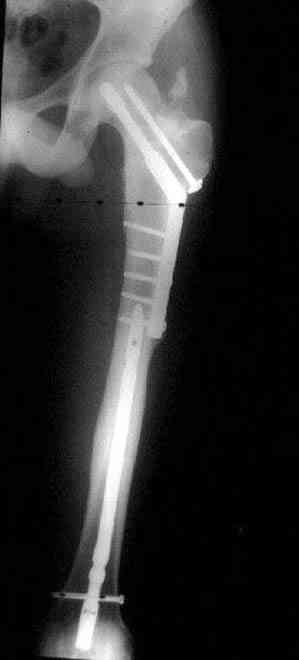

Уважаемые коллеги. Благодарим за дискуссию. Мы решили выполнить комбинированную операцию - эндопротезирование тазобедренного сустава и ретроградный интрамедуллярный остеосинтез (одномоментно)

После удаления штифта нет необходимости проведения "стресса" на сращение, лучше провести фиксацию пластиной по два шурупа с каждой стороны.

Минимальный перкутанный доступ без ущерба сохранит сомнительное мозолеобразование и создаст условия для профилактики ложного сустава бедра.

Или при наличии ретроградной техники, короткий штифт с одним блокирующим шурупом дистально, создаст адекватную фиксацию и условия для быстрейшего восстановления.